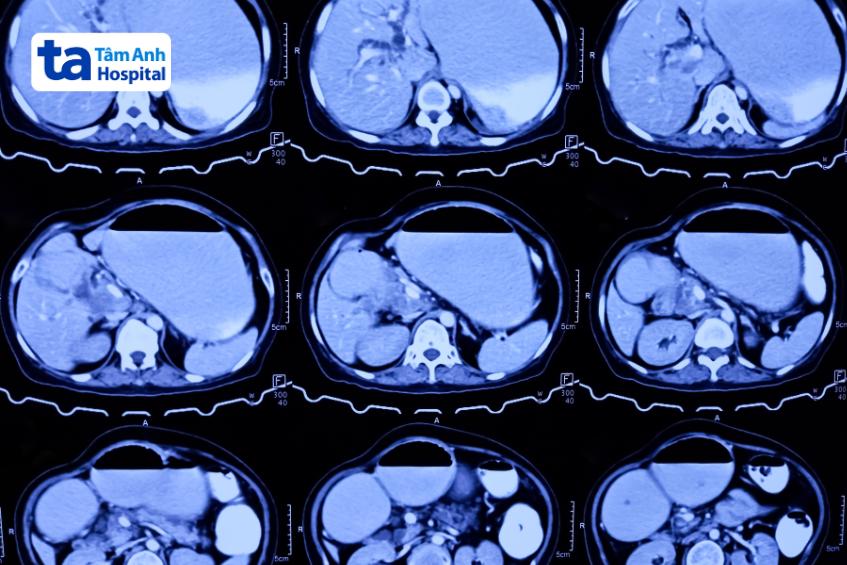

Đối với những bệnh nhân có khối u ở bụng, chụp CT có tiêm thuốc cản quang là lựa chọn được ưu tiên. Trên CT, GIST xuất hiện dưới dạng một khối rắn, tăng cường độ tương phản với bờ mịn. Ở những bệnh nhân lo ngại tiếp xúc với tia bức xạ hoặc không thể tiêm chất cản quang có chứa i-ốt, bác sĩ sẽ chỉ định chụp MRI.